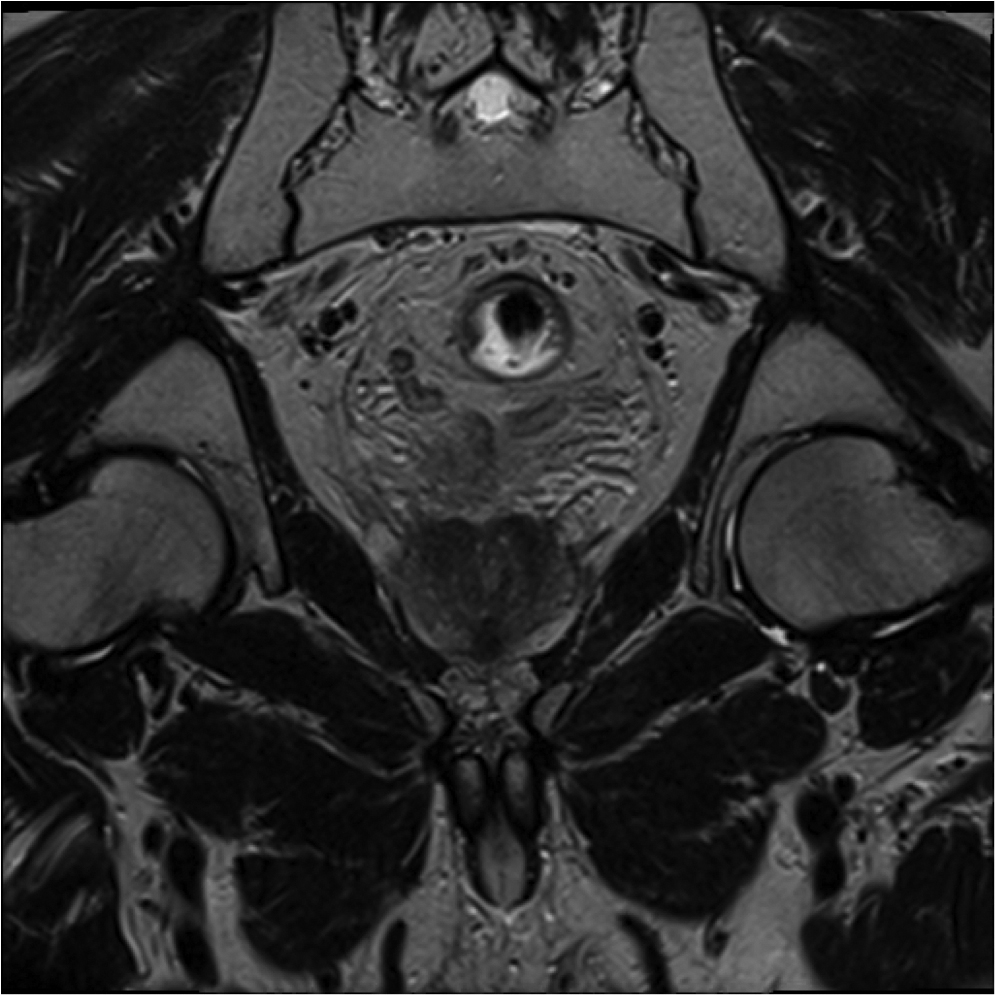

Fig1. Pacient cu neoplasm rectal stadiul IIIC (T3; N2; M0) confirmat bioptic, adenocarcinom mixt G2

a-d imagini T2 ponderate în plan sagital, oblic axial și oblic coronal – masă tisulară dezvoltată superior de joncțiunea anorectală, lateral dreapta, cu minimă extensie la nivelul grăsimii mezorectale și limfoganglioni mezorectali cu diametru de până la 10 mm;